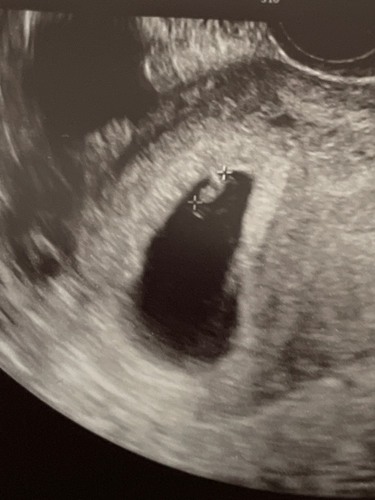

Ik wil je zeker niet ontmoedigen maar het doet me wat denken aan mijn missed abortion in januari.

Ook zwanger geworden dmv letrozole en ovitrelle. Ik was 7 weken en de embryo had de grootte van 6 weken en geen hartslag. Mijn echo leek zelfs op die van jouw (kijk maar in mijn dagboek). Ik heb op aanraden van de gyne ook een weekje afgewacht maar ze heeft wel mijn bloed geprikt en toen was het duidelijk dat mijn hcg stijging ook echt niet goed was.

Wilt natuurlijk niet zeggen dat dit ook jouw verhaal wordt.